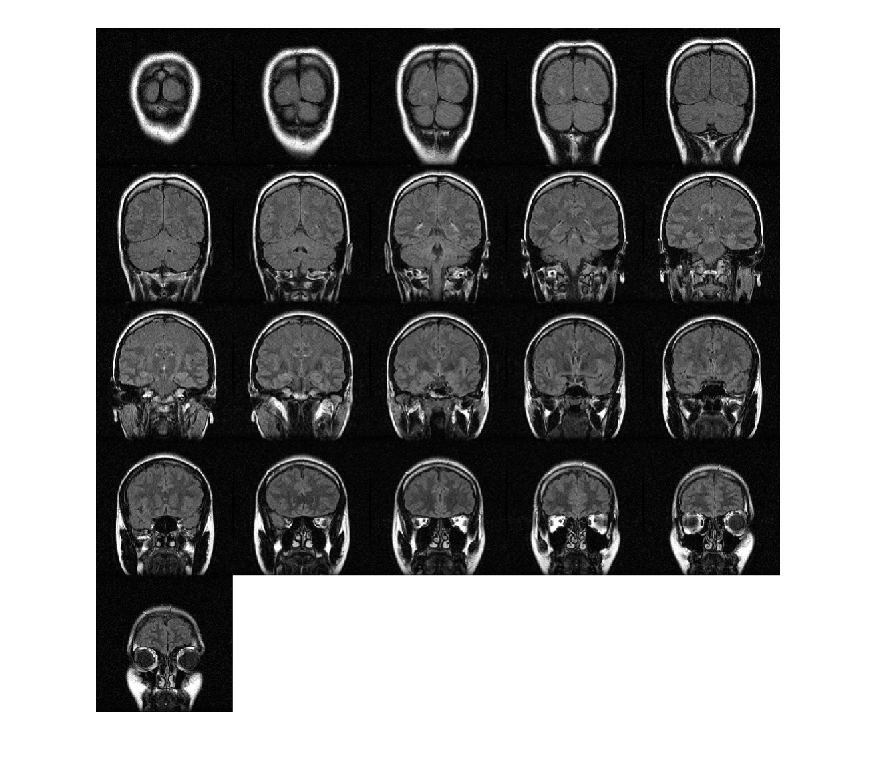

Загрузите объем MRI. Этот объем хранится как 4-D массив с одноэлементной размерностью. Создайте 3-D полутоновый объем при помощи squeeze функция, чтобы удалить одноэлементную размерность.

load mri;

V = squeeze(D);

Отобразите плоскости объема.

montage(D,'BackgroundColor','w')

Figure contains an axes. The axes contains an object of type image.